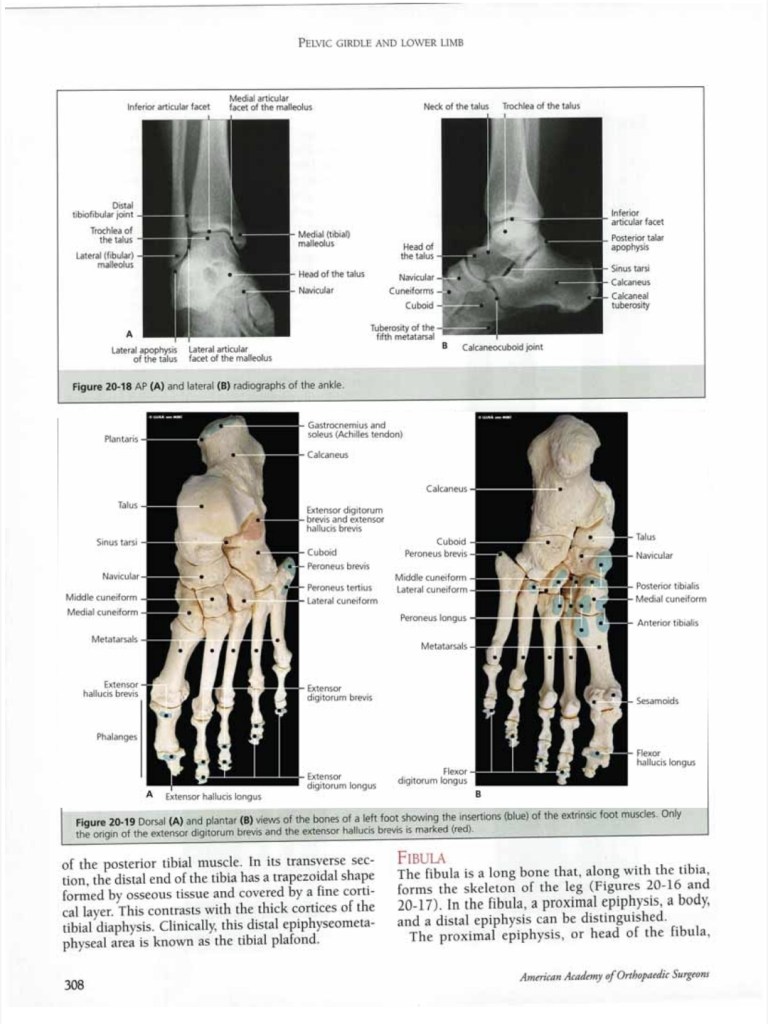

Lecture Anatomy lower limb 1